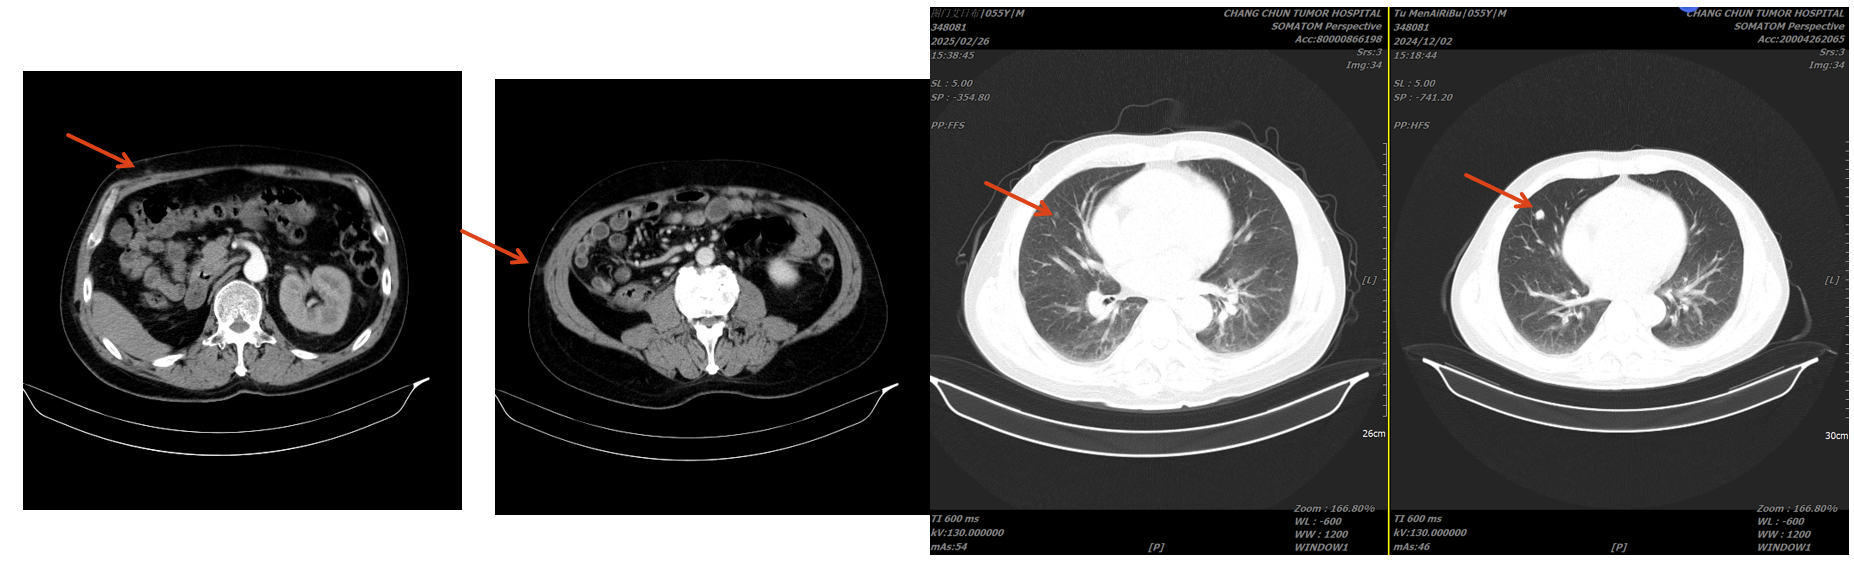

治疗与复查经过

手术治疗

行经腹右肾根切除术治疗。术后病理:透明细胞性肾细胞癌,肿瘤侵犯肾纤维被膜,局部紧邻肾周脂肪几肾盂,未侵犯肾窦脂肪。T3N0M1。

术后系统治疗

培唑帕尼片800mg,口服,一日一次。

特瑞普利单抗注射液240mg,ivgtt,每两周一次

地舒单抗120mg sc,每28日一次。

放疗计划:右侧肩胛骨、肋骨转移灶 GTV 3600cGy/300cGy/12f。

疗效评估

患者口服培唑帕尼耐受较好,无明显骨髓抑制表现,胆红素正常,但谷氨酰胺转肽酶,谷草转氨酶,碱性磷酸酶仍升高。病灶稳定。